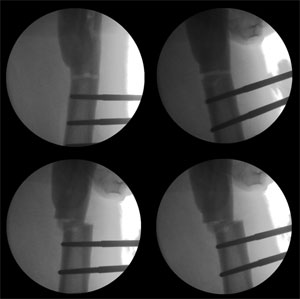

The pictures taken during surgery, showing the position of the Schanz screws and their orientation in different planes. |

| The C-arm pictures of correction of the angulation and translation. Clockwise from top left –osteotomy above the lower group of screws, correction of angulation making the screws parallel, translation of the fragments relative to each other, final adjustment of angles and translation. |